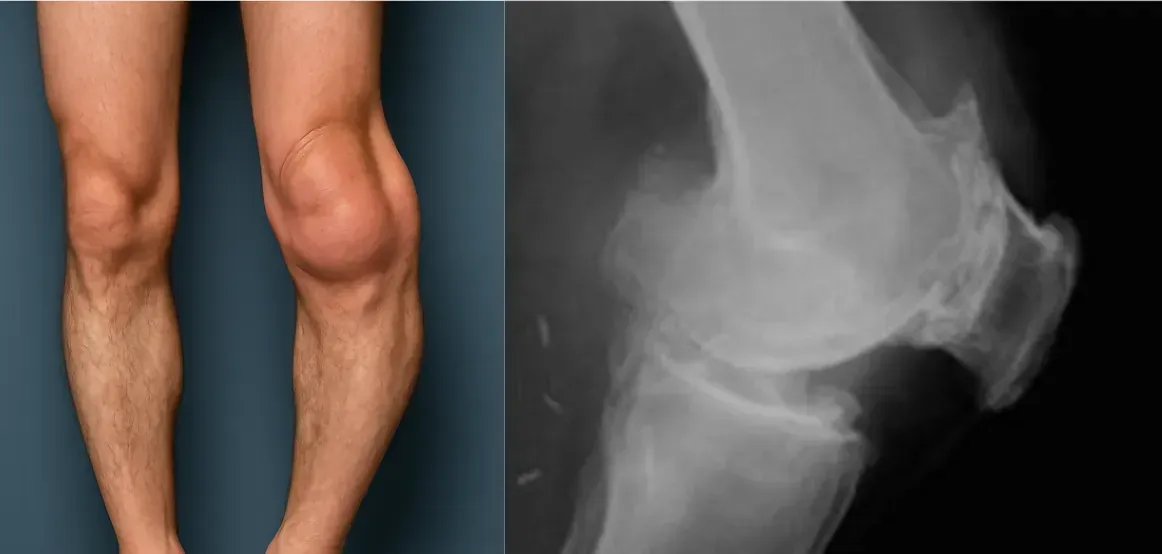

Vorher konnte ich die Knie kaum ganz beugen und strecken, jetzt gleiten alle Gelenke. Ich finde, einen Versuch ist es wert! Ich gehe wieder mit den Enkeln spazieren und freue mich sehr!

Ingrid, bestellen Sie ruhig! Mir drohte auch eine Gelenkersatz-OP. Zum Glück habe ich Veluflex noch ausprobiert – nach 2,5 Monaten war die Erkrankung weg.

Mit den Beinen hatte ich schon lange Probleme. Nach 2 Jahren machte der Rücken nicht mehr mit. Ich dachte, es sei vorbei. Im letzten Jahr konnte ich kaum noch normal gehen. Auf Veluflex hatte ich nicht gehofft – aber es hat fast sofort geholfen. Ich fühle mich mindestens 30 Jahre jünger. Und ich bin 82!